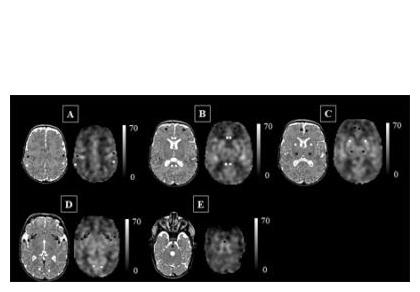

Les scientifiques aboutissent à des cartes du flux sanguin cérébral exprimé en mL / 100g / mn et montrent que, chez ces enfants, l'insula (flèches noires sur « D ») peut être particulièrement vulnérable aux stress supplémentaires de la vie. Ainsi, le flux sanguin cérébral de zones clés du cerveau peut être altéré chez les prématurés, ce qui peut constituer un signe précurseur d'une perturbation du développement cérébral bien avant que l'imagerie conventionnelle soit en mesure de la détecter.

Le débit sanguin cérébral, un bon marqueur du développement cérébral de l’enfant : ici, les chercheurs parviennent à cartographier, chez 98 nouveau-nés prématurés nés à moins de 32 semaines gestationnelles à la naissance et pesant moins de 1.500 grammes à la naissance, le débit sanguin cérébral, par imagerie par marquage de spins artériels. La technique non invasive identifie la concentration en eau du sang qui circule dans le cerveau des nourrissons afin d’identifier les zones qui reçoivent ou ne reçoivent pas le sang adéquat. Cette analyse montre que les nourrissons très prématurés présentent un débit sanguin cérébral cortical supérieur à celui des nourrissons nés à terme, mais que, dans certaines zones, dont l'insula -impliquée dans l'émotion-, le cortex cingulaire antérieur - impliqué dans les processus cognitifs- et le cortex auditif -impliqué dans le traitement du son- le débit sanguin est significativement diminué par rapport à celui de nourrissons nés à terme. Et, corrélées à ces déficiences de débit sanguin, sont identifiées des lésions cérébrales parenchymateuses.

« La maturation continue du cerveau du nouveau-né est illustrée par le schéma de distribution du flux sanguin cérébral. Grâce à cette technique d’imagerie, notre étude montre qu'en plus du tronc cérébral et de la matière grise profonde, l'insula et les zones du cerveau responsables des fonctions sensorielles et motrices sont également parmi les régions les plus oxygénées. Or, chez les nourrissons prématurés, l'insula peut être particulièrement compromise et donc vulnérable aux stress supplémentaires que l’enfant pourra rencontrer dans la vie. Ainsi, le développement altéré de l'insula et du cortex cingulaire antérieur chez ces nouveau-nés pourrait constituer les signes avant-coureurs du risque de troubles neurodéveloppementaux à long terme ».